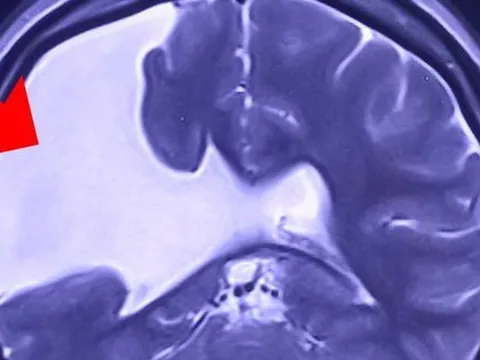

Người phụ nữ gần 30 năm sống chung với nứt não

Một phụ nữ trẻ bị nứt não hiếm gặp từ nhỏ nhưng không biết, đến nay vết nứt mở rộng gây động kinh co giật nghiêm trọng và vừa được bác sĩ mở sọ giải áp.